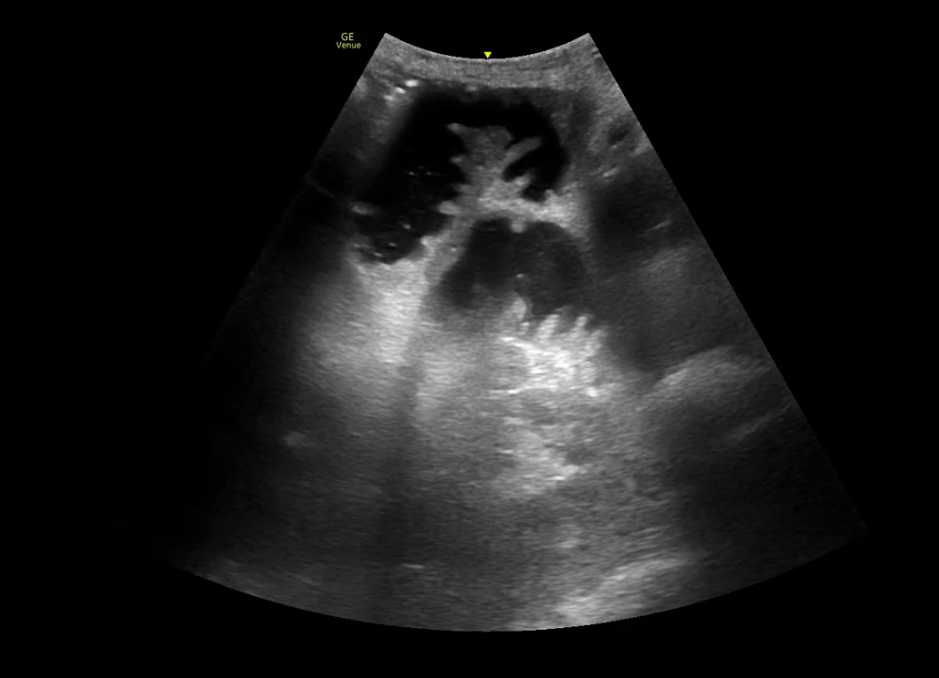

Ante AP de cirugía, dolor abdominal y vómitos, se realiza rx abdominal que resulta normal. Dada la alta sospecha, se realiza ecografía: gran cámara gástrica con contenido en su interior con dinámica «en lámpara de lava». Además, asas de intestino delgado dilatadas (diámetro 2,9 cm) con movimiento de peristalsis y rebote y edema de pared. Compatible con obstrucción intestino delgado.

Utilidad de ecografía abdominal en el ámbito de Urgencias hospitalarias o de Atención Primaria ante dolor abdominal agudo, en concreto para diagnóstico de obstrucción intestinal ante la sospecha y falta de radiografía simple de abdomen o ausencia de hallazgos sugestivos de la misma en la Rx abdominal simple y alta sospecha clínica.